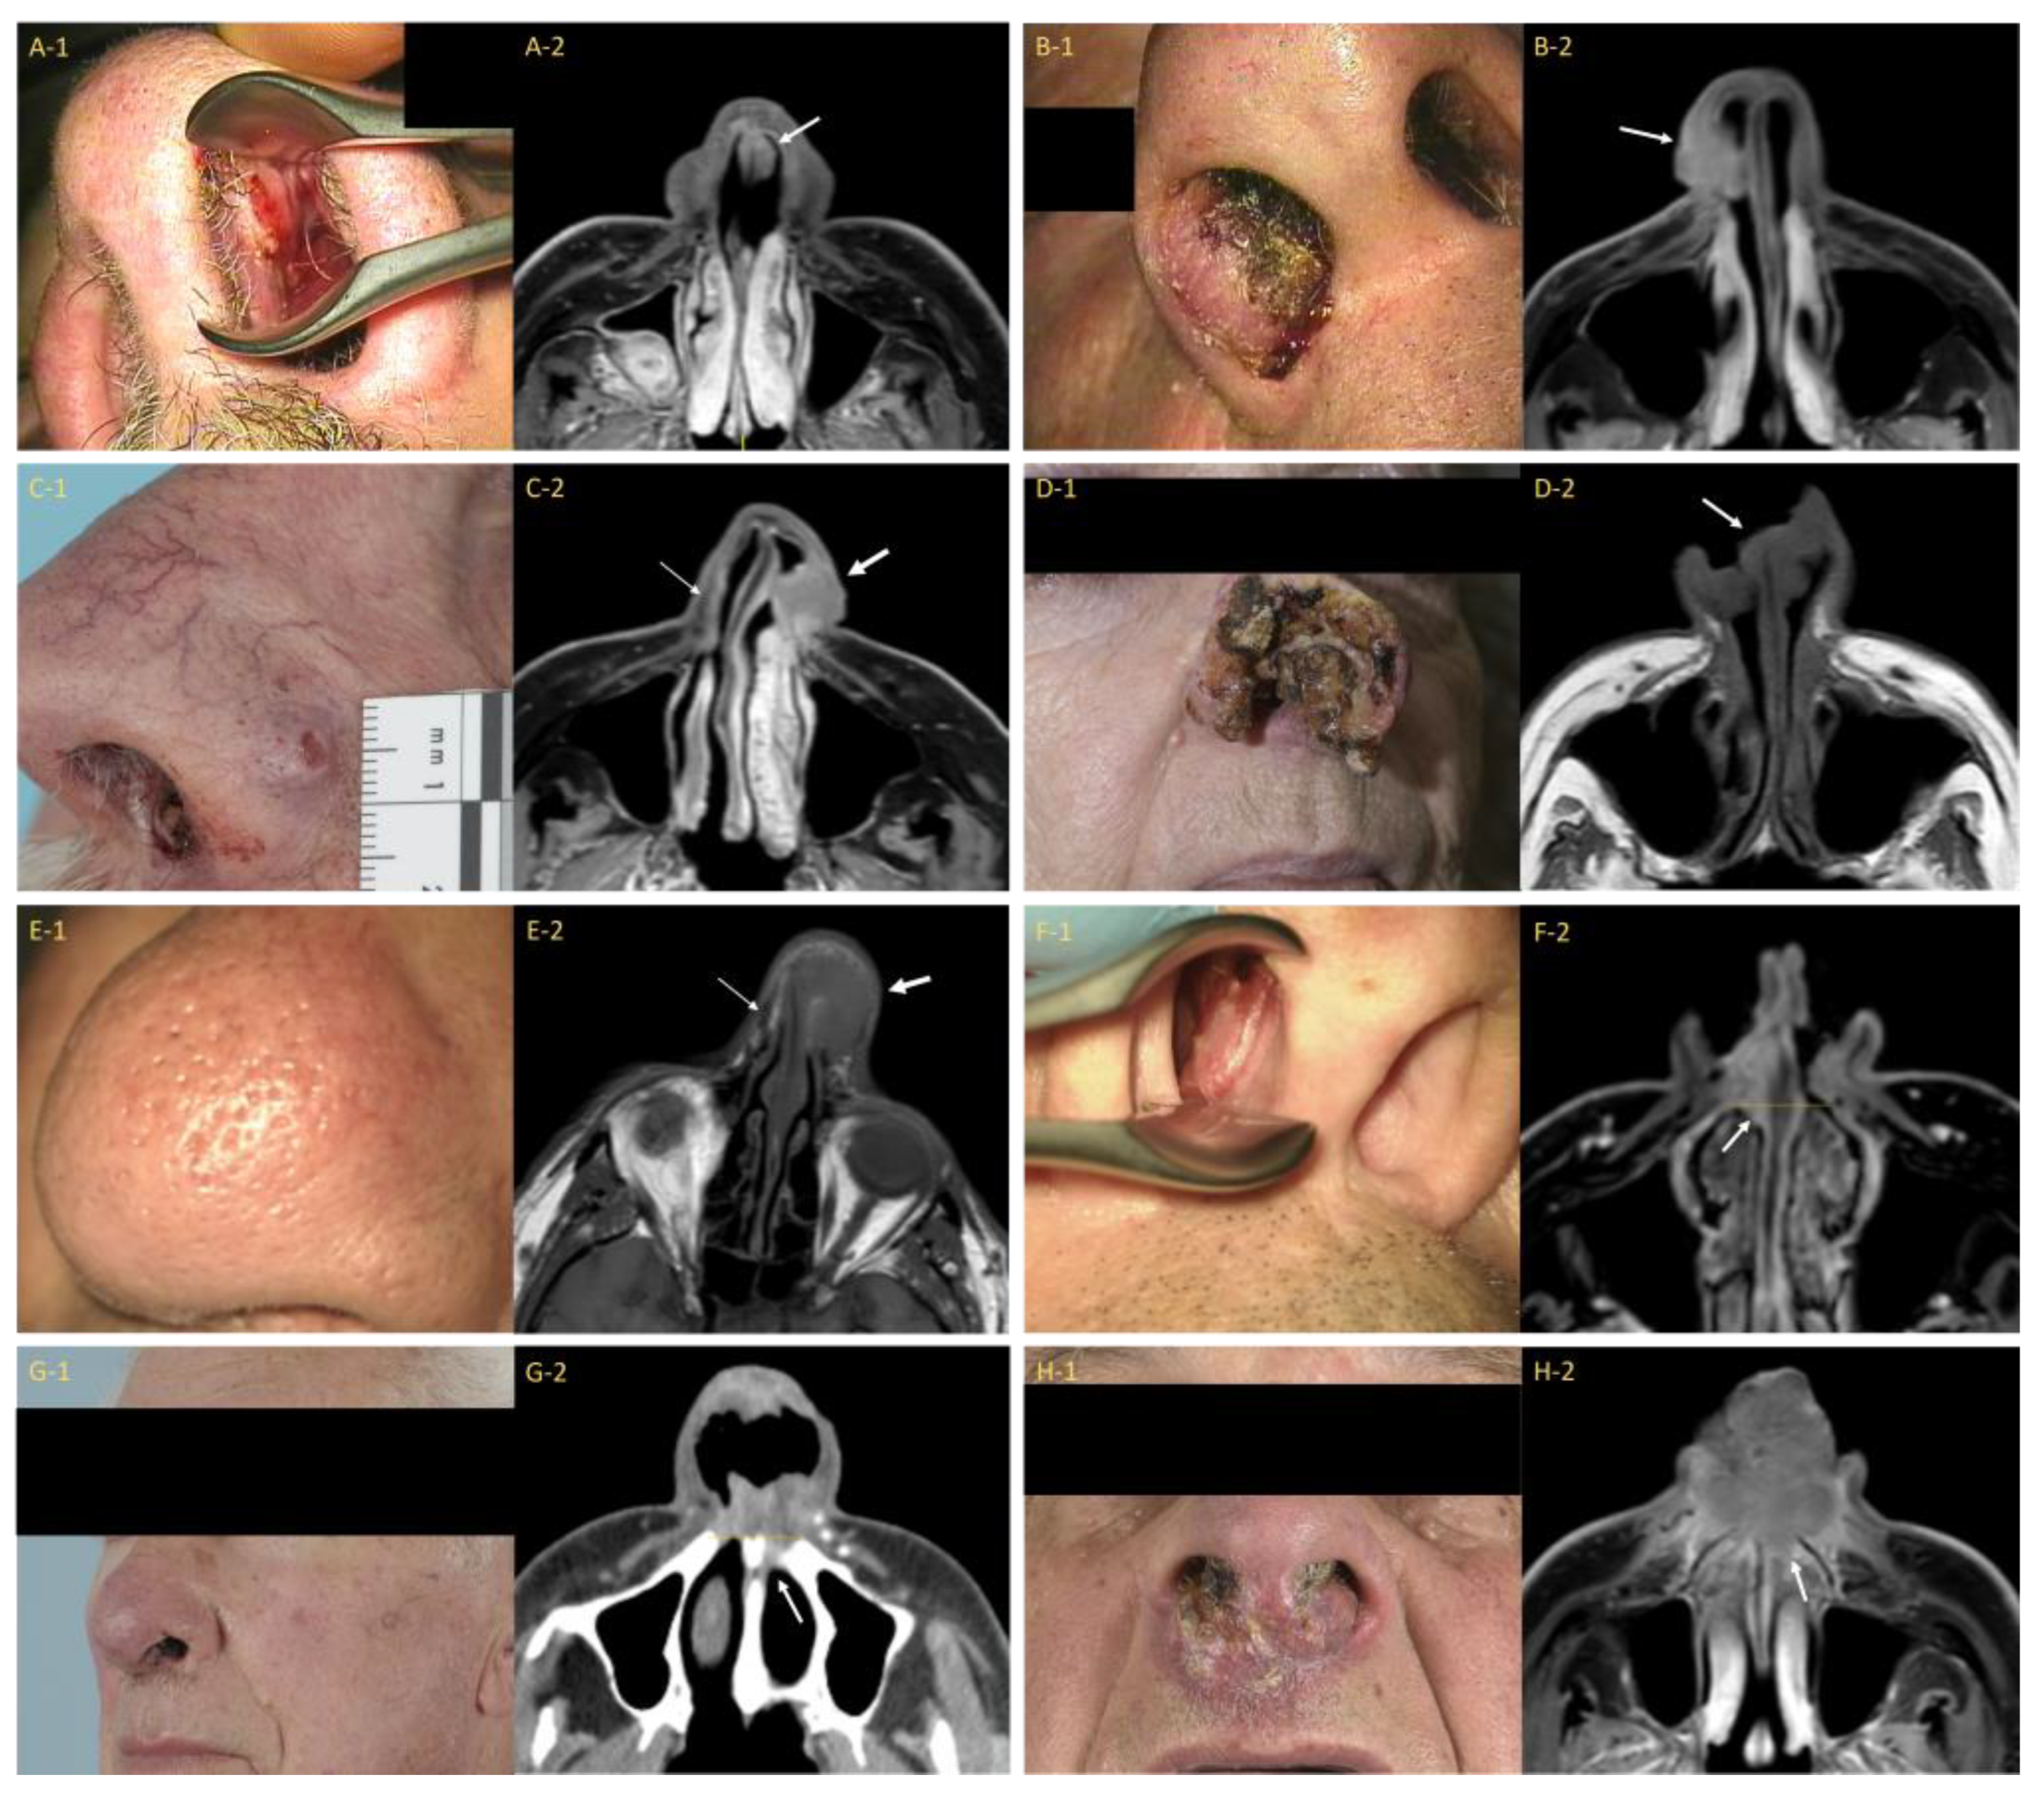

This classification was originally proposed by Bussu et al., who built on Wang’s system but incorporated clearly delineated anatomical landmarks to differentiate between the stages [23]. It defines the nasal vestibule as the area extending from the plane tangential to the pyriform aperture to the nostrils. Tumors are upstaged based on the invasion of the skin of the face or external nose (T2a), cartilage invasion (T2b), posterior extension beyond the pyriform aperture (T3), bone invasion (T4a), and the invasion of adjacent vital structures such as the orbit or anterior cranial base (T4b). An overview of the clinical images and corresponding imaging studies is provided in Figure 3. This classification aims to be both easy to use in clinical practice as well as providing a better indicator of prognosis compared to existing classifications. The prognostic value of this classification still requires additional validation.

Figure 3.

Clinical photographs and corresponding imaging studies of patients with a carcinoma of the nasal vestibule for each stage of the Bussu et al. classification. (A-1) = Patient with a left-sided T1 carcinoma of the nasal vestibule (CNV); (A-2) = Corresponding axial postcontrast T1-weighted MR image with fat saturation (T1 MR Gd FS) showing subtle soft tissue thickening on the left side of the nasal septum (white arrow); (B-1) = Patient with a right-sided T2a CNV (caudal ala); (B-2) = Corresponding axial T1 MR Gd FS image displaying the tumor invading the cutis (white arrow); (C-1) = Patient with a left-sided T2b CNV with extension through the alar cartilage to the external skin of the nose; (C-2) = Corresponding axial T1 MR Gd FS image showing cartilage invasion and an irregular skin contour (thick white arrow). Compare to the contralateral side where the normal (low signal intensity) alar cartilage is visible (thin white arrow); (D-1) = Patient with a T2b CNV with extensive tissue destruction; (D-2) = Corresponding axial T1 MR Gd FS image showing the (bilateral) tumor (white arrow); (E-1) = Patient with a left-sided T2b CNV with peau d’orange suggesting the invasion of the (sub)cutis; (E-2) = Corresponding axial T1 MR Gd FS image. Note: absence of the alar cartilage (thick white arrow). Normal (low signal intensity) alar cartilage is present on the contralateral side (thin white arrow); (F-1) = Patient with a right-sided T3 CNV; (F-2) = Corresponding axial T1 MR Gd FS image shows tumor extension (white arrow) beyond the plane of the pyriform aperture (yellow line); (G-1) = Patient with a left-sided T3 CNV; (G-2) = Corresponding axial postcontrast CT image showing extension (white arrow) beyond the plane of the pyriform aperture (yellow line); (H-1) = Patient with a T4a CNV; (H-2) = Corresponding axial T1 MR Gd FS image displaying extension of the tumor into the anterior maxilla (white arrow).